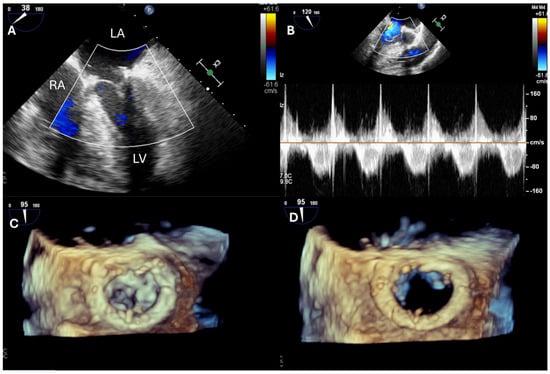

| TV repair | Describe TR mechanism Describe TV anatomy Measure TV annulus | Exclude iatrogenic TV stenosis |